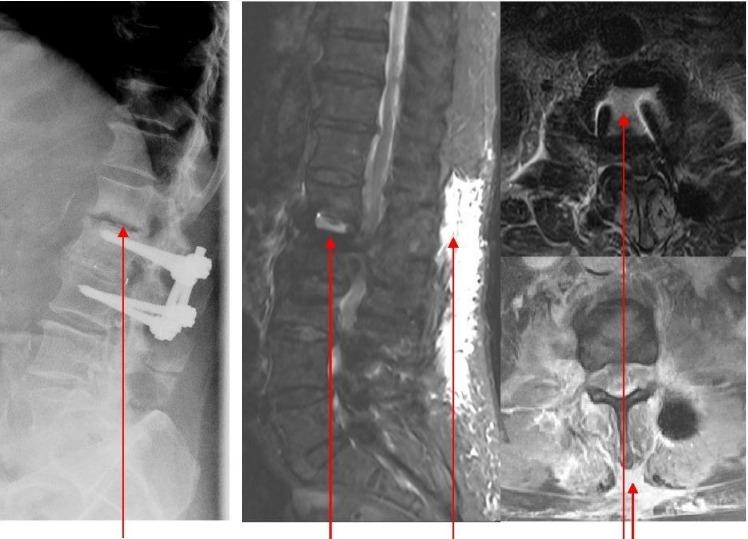

Specific and non-specific infections of the spine are rare. Due to their potential for severe instabilities, deformities and the impairment of neurological structures, the treatment is often prolonged and needs an interdisciplinary management. The clinical presentation is uncharacteristic, therefore diagnosis is often delayed. There are no prospective randomized studies for therapy recommendation. The surgical concept includes eradication of the infection and the reliable stabilization of involved segments. This concept is successful in most cases of endogenous vertebral osteomyelitis. The therapy of the exogenous spine infections after macro and micro surgery is more difficult, due to the critical wound situation and the involvement of the posterior parts of the spine. In these cases, infection-associated instability of the anterior part is complicated by critical posterior wound conditions. We present three cases of severe exogenous vertebral infections, where temporary external transpedicular spine fixation was used for salvage procedure, till soft tissue conditions have permitted a definitive internal stabilization.

脊柱的特异性和非特异性感染较为罕见。由于它们可能导致严重的不稳定、畸形以及神经结构受损,治疗往往较为漫长,且需要多学科管理。临床表现不典型,因此诊断常常延迟。目前尚无用于推荐治疗方法的前瞻性随机研究。手术理念包括根除感染以及对受累节段进行可靠的稳定固定。这一理念在大多数内源性椎体骨髓炎病例中取得了成功。由于伤口情况危急以及脊柱后部受累,宏观和微观手术后外源性脊柱感染的治疗更为困难。在这些病例中,前部感染相关的不稳定因后部伤口情况危急而变得复杂。我们展示了三例严重的外源性椎体感染病例,其中采用了临时经椎弓根外固定脊柱进行挽救手术,直至软组织条件允许进行最终的内固定。